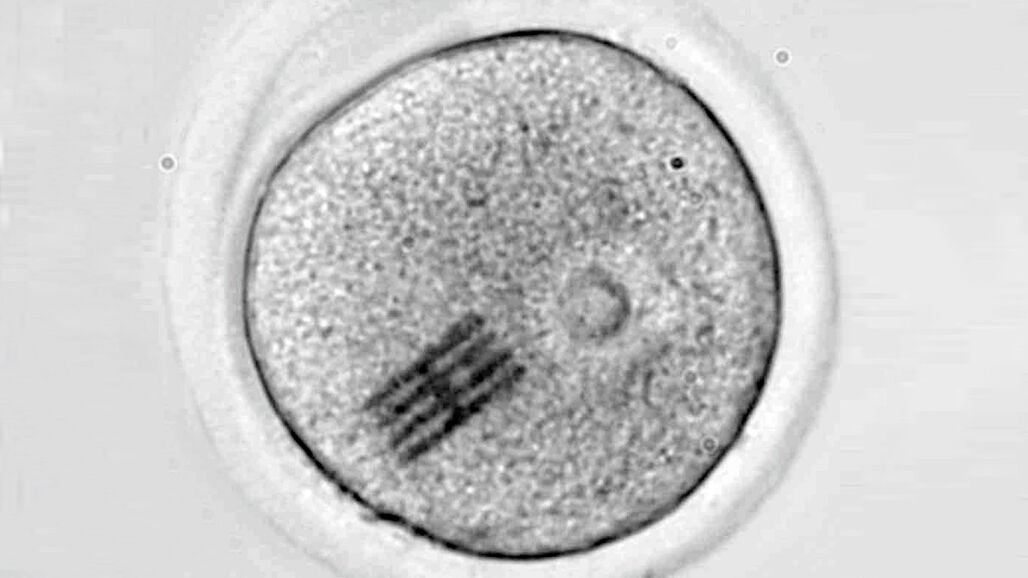

La investigación, liderada por un equipo del centro Next Fertility Murcia y la Universidad de Murcia, identificó diversos tipos de microplásticos —como polietileno (PE), polipropileno (PP), poliuretano (PU), PVC o teflón (PTFE), entre otros— en muestras extraídas de 25 mujeres y 18 hombres. Los fluidos foliculares, recogidos durante procedimientos de aspiración ovárica, mostraron una mayor concentración de microplásticos en comparación con las muestras de semen.

Los análisis se realizaron mediante microscopía infrarroja por láser (LDIR), tras un proceso de mineralización para eliminar componentes orgánicos. Como medida de control, se verificó que los recipientes utilizados no estaban contaminados previamente.